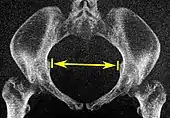

| Pelvic inlet | Transverse diameter of the pelvic inlet | ![]() |

![]() Coronal plane |

The iliopectineal lines, at widest transverse distance. | 13 to 14.5 cm.[4] |